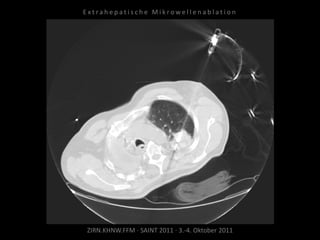

Patient: Männlich, 64 Jahre

Diagnose: Bronchial-Ca rechts, Z.n.

Pneumonektomie,

neu aufgetretene, solitäre, im Verlauf

progrediente Metastase im Oberlappen

links.

Ablation am 27.11.2010

1 Nadelposition.

Kontrolle nach MWA:

Parenchymeinblutung, Pneumothorax.

Noch im CT Anlage einer Pleuradrainage.

Patient am Abend beschwerdefrei.